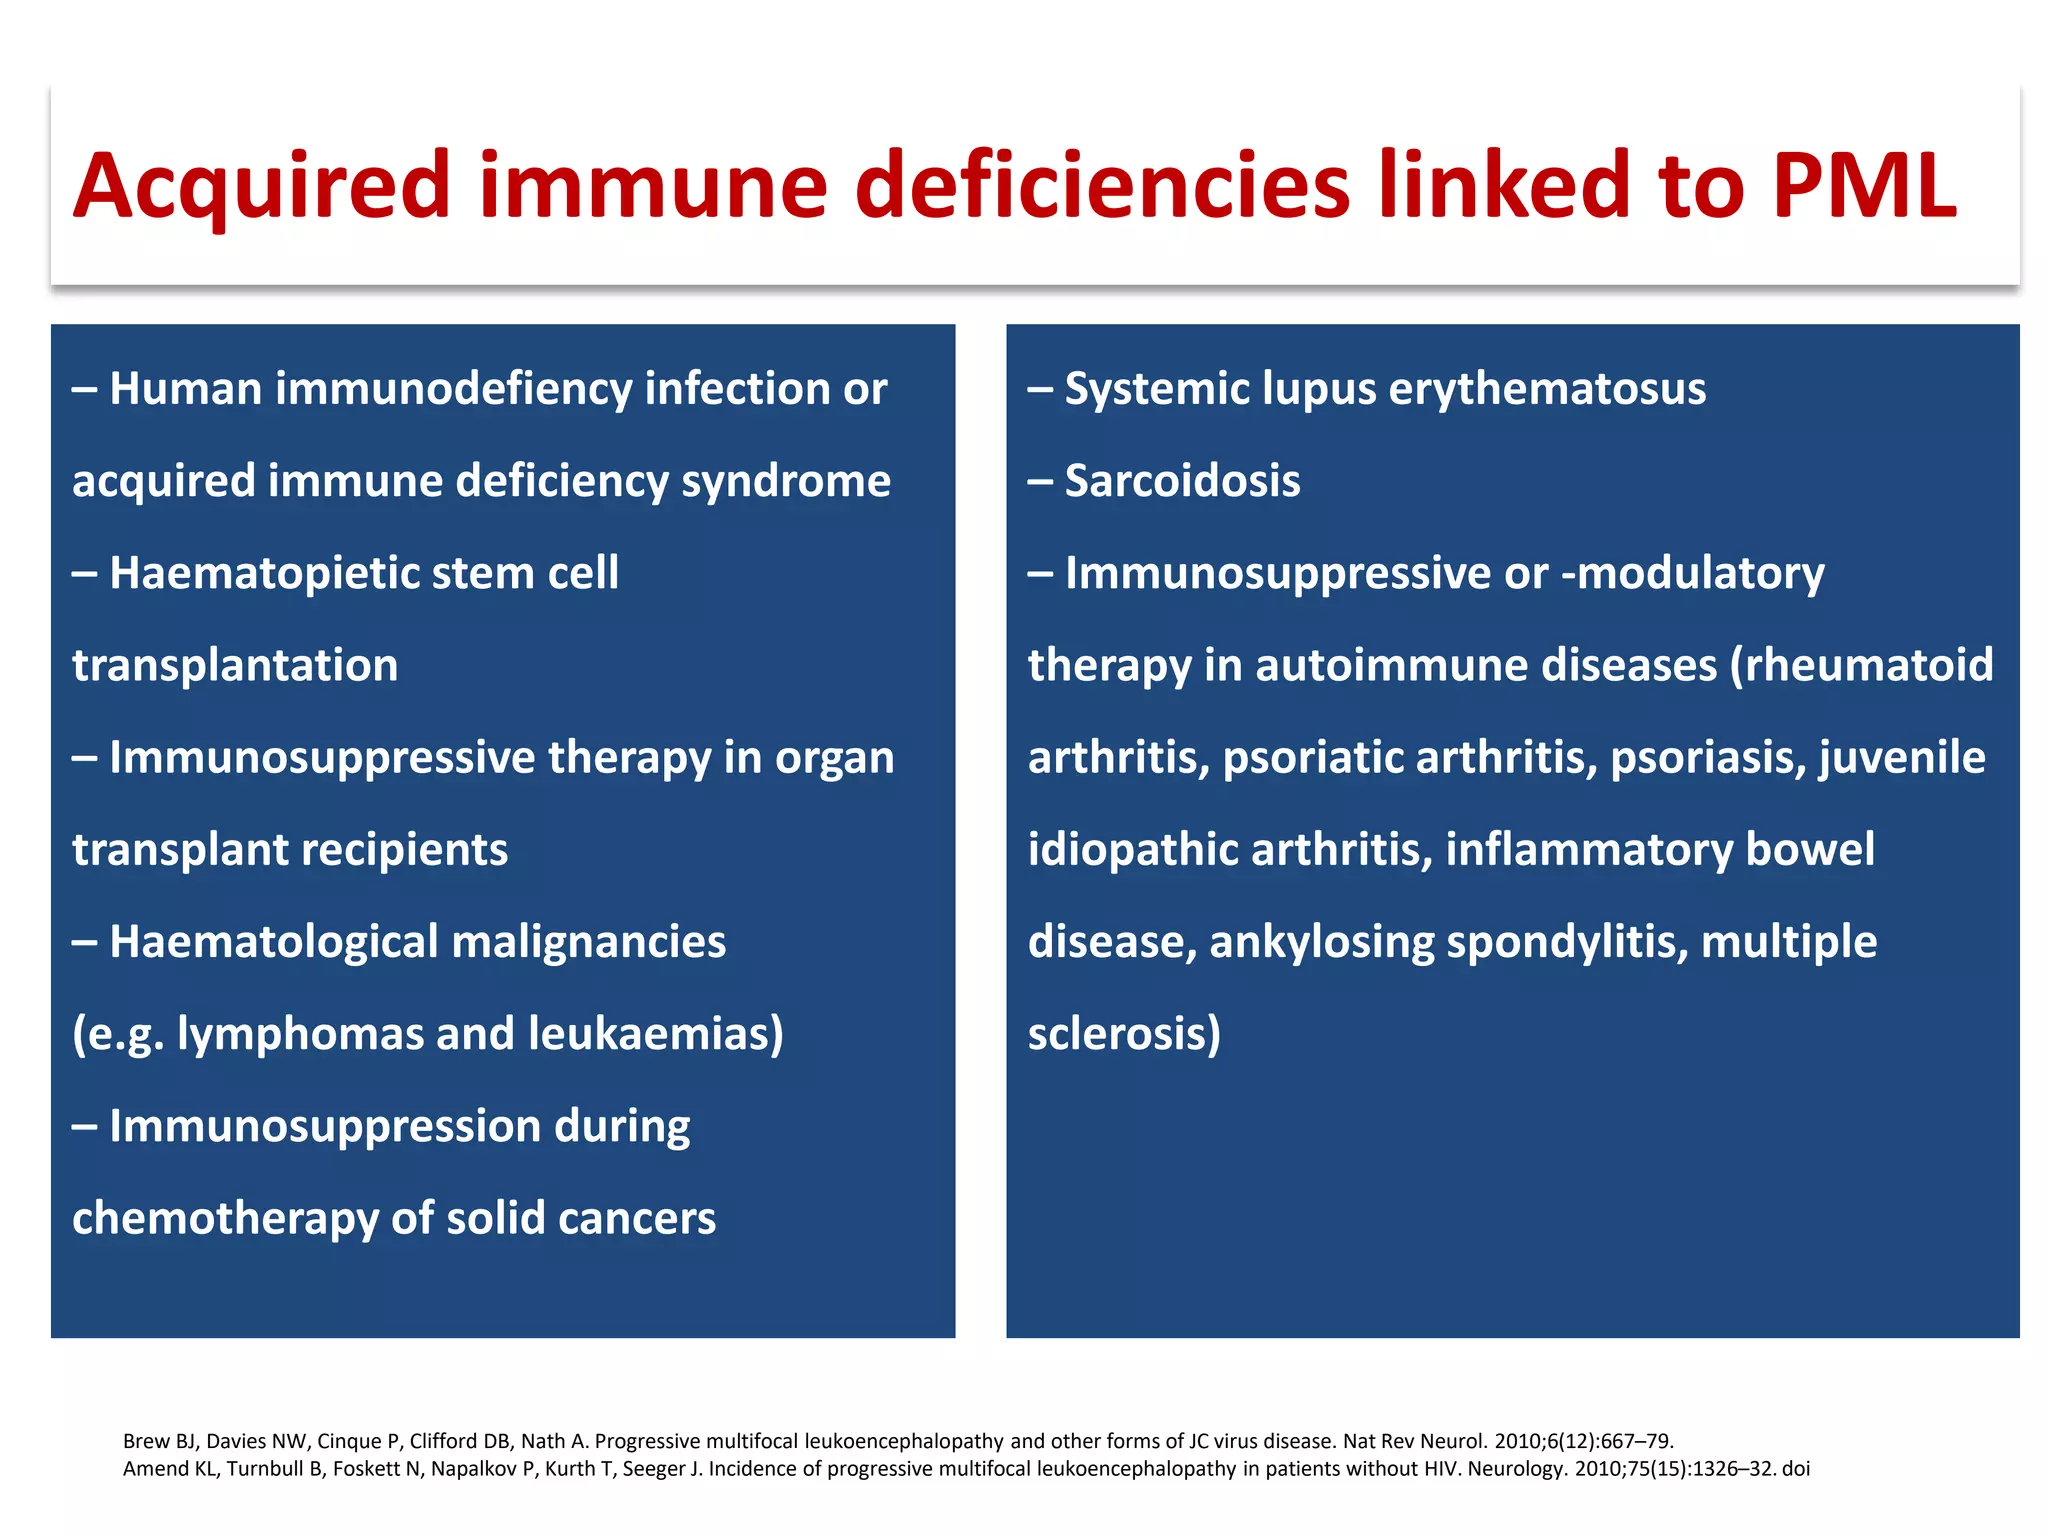

This document discusses progressive multifocal leukoencephalopathy (PML), an opportunistic infection caused by the John Cunningham virus (JCV) that leads to demyelination in the central nervous system. It highlights the epidemiology, clinical manifestations, diagnostic methods, and risk factors associated with PML, particularly in immunocompromised patients and those undergoing immunomodulatory therapies. It also presents data on the incidence of PML in patients treated with natalizumab and other therapies, addressing the relationships between these treatments and the development of PML.